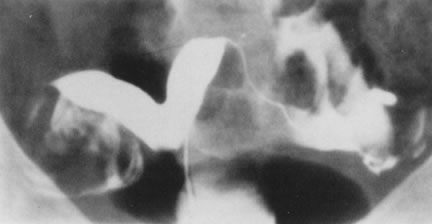

Fig. 27. Hysterosalpingogram shows a divided uterine cavity.

Fig. 29. Postoperative hysterosalpingogram shows normal uterine cavity.